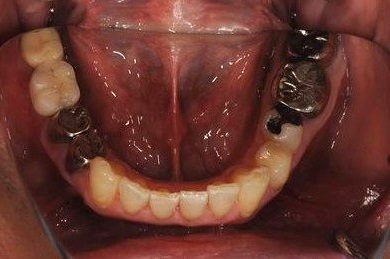

インプラントの症例写真 IMPLANT

| 性別/年齢 | 男性 / 57歳 | ||||||||||||||||||||||||||||||||

| 主訴 | 右奥歯のブリッジが取れ、支柱の2本の歯が痛むため、インプラント治療を希望。 | ||||||||||||||||||||||||||||||||

| 治療内容 | インプラント2本、ハイブリッドセラミック2本 | ||||||||||||||||||||||||||||||||

| 総治療費 | 533,610円 | ||||||||||||||||||||||||||||||||

| 治療期間 | 1年0ヶ月 |